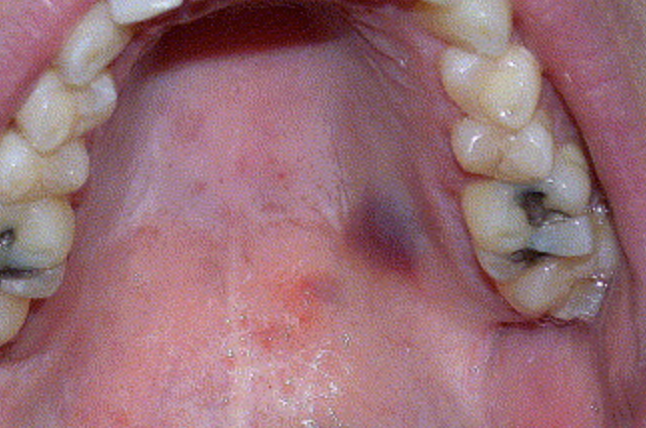

Karposi’s Sarcoma

Abnormal Findings for 5. Hard (anterior) and soft (posterior) palates and width

Deep purple, raised, or flat lesions